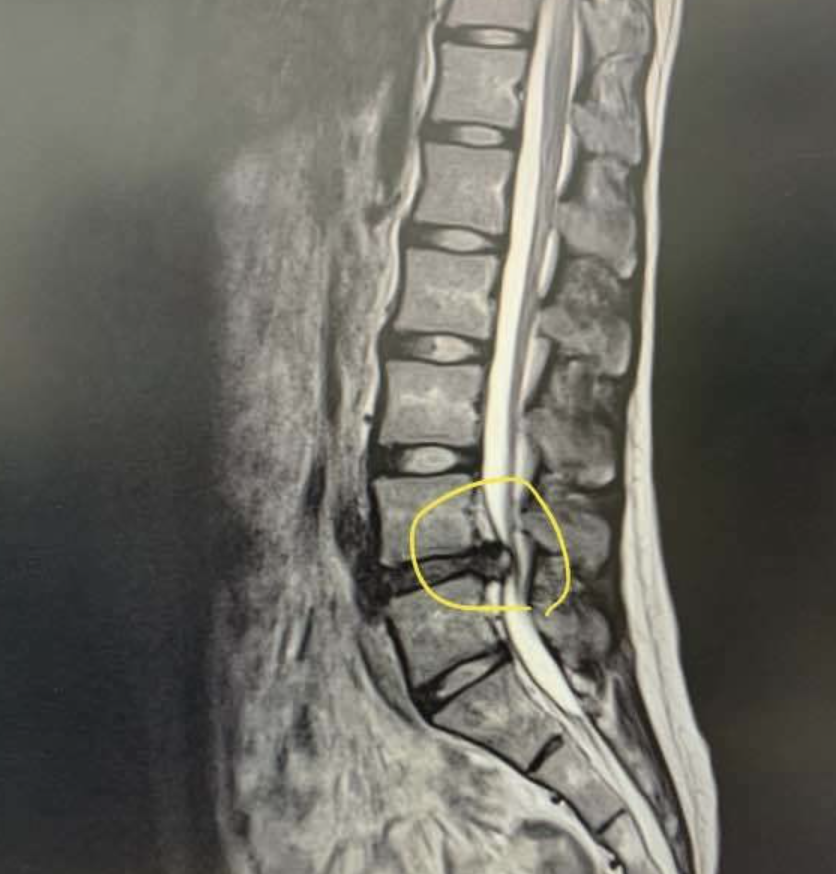

7. 허리디스크 진단 mri

헤르니아 디스크는 일반적으로 다음의 조합을 통해 진단됩니다.

- 이미징 테스트: MRI는 탈장된 디스크를 진단하는 데 사용되는 일반적인 이미징 테스트입니다. 척수, 신경 및 주변 조직의 상세한 이미지를 제공하고 탈출의 위치와 크기를 보여줄 수 있습니다.

경우에 따라 진단을 확인하거나 유사한 증상을 유발할 수 있는 다른 조건을 배제하기 위해 CT 스캔 또는 X-레이를 사용할 수도 있습니다.

탈장된 디스크가 진단되면 의사는 필요한 경우 비수술적 옵션이나 수술을 포함할 수 있는 적절한 치료 과정을 추천할 것입니다.